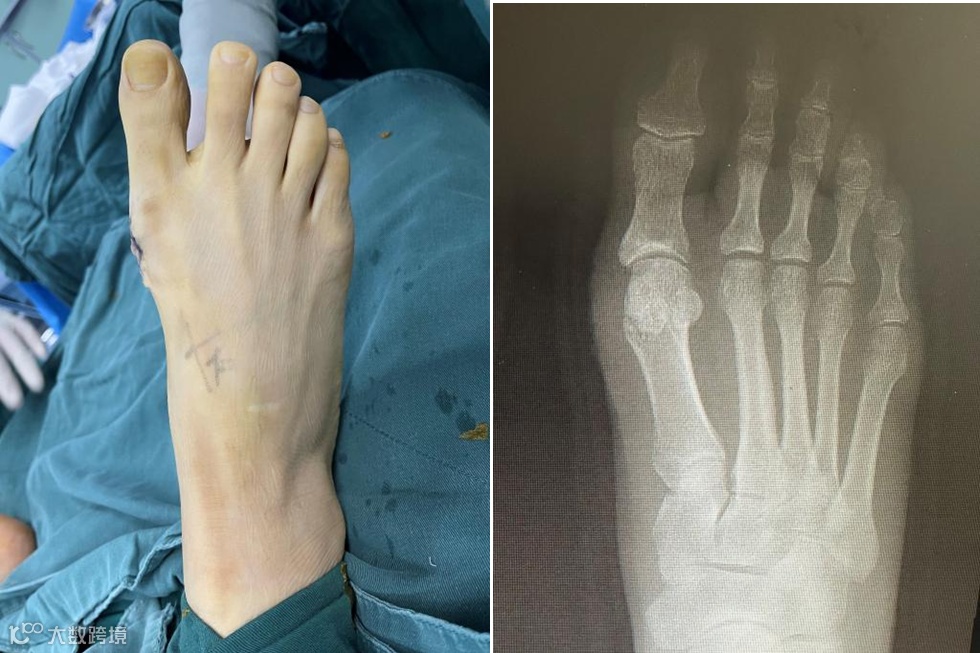

入院当日医生对小米开展相关检查,第二日即行踇外翻畸形矫形术,耗时仅30分钟即术毕。为了带给小米更佳的治疗体验,主刀医师使用了皮内缝合术,让小米的脚几乎不留疤痕,术后第一天即可下地活动。

术后第一天早上医生查房时,看到小米拿出早已准备好的高跟鞋正在试穿,对查房医生说:“脚型好看了,穿高跟鞋不疼也不磨脚了!终于可以轻松地进行体育锻炼了!”她那份开心的劲儿,真的感染了周围的人。